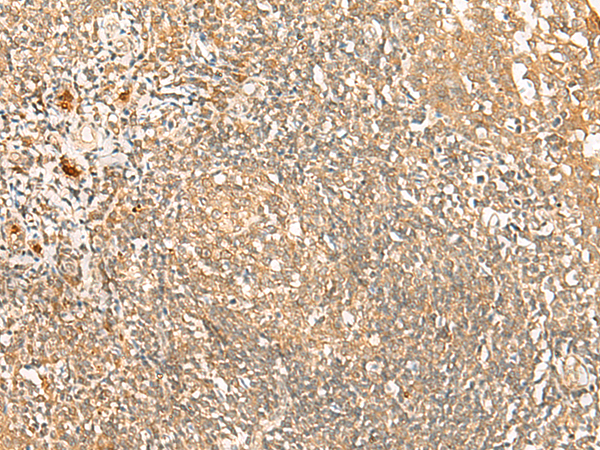

分类: 科研抗体货号: P43585别名: ZAQ; PKR1; GPR73; PK-R1; GPR73a应用: IHC反应种属: Human